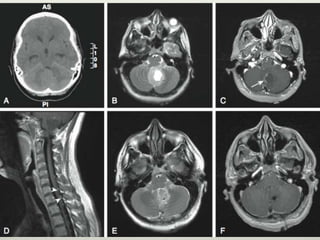

Resonancia

• Iso hipointensa en T1

• Hiperintensa en T2

• Heterogénea al medio de contraste

Diseminación leptomeningea

• La médula espinal - sitio más común.

• La mayoría de las metástasis se

encuentran a lo largo del borde

posterior de la médula espinal.

• Flujo del LCR de cisterna magna

al margen posterior de la

médula espinal

Resonancia • Iso hipointensaen T1 • Hiperintensa en T2 • Heterogénea al medio de contraste

Diseminación leptomeningea • Lamédula espinal - sitio más común. • La mayoría de las metástasis se encuentran a lo largo del borde posterior de la médula espinal. • Flujo del LCR de cisterna magna al margen posterior de la médula espinal